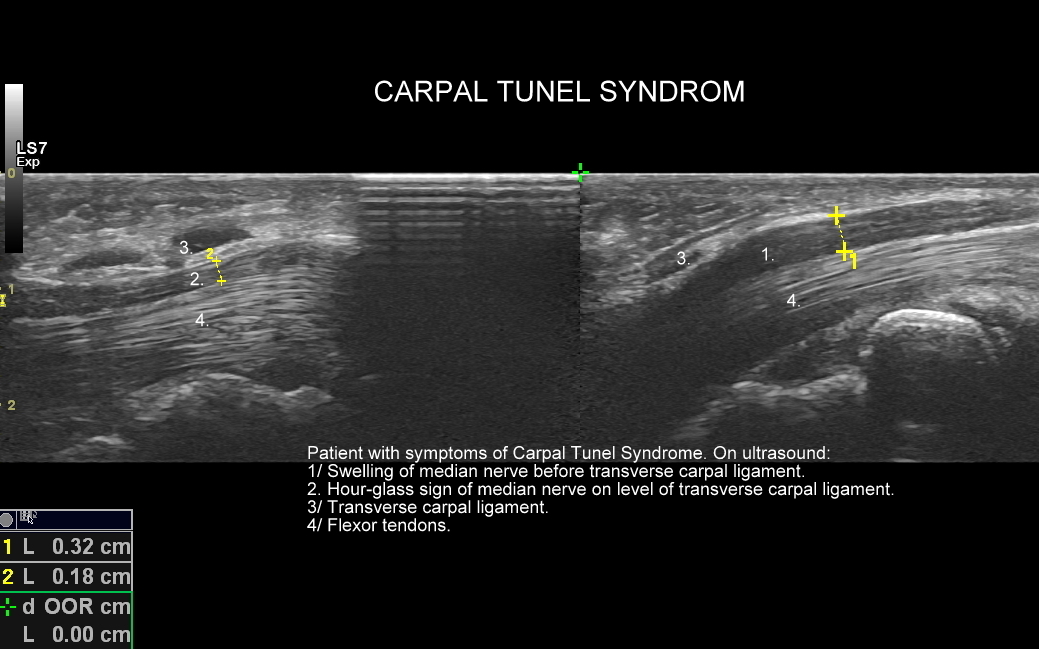

Badanie USG jest podstawową metodą diagnostyczną nadgarstka, ręki oraz palców. Pozwala z łatwością ocenić nerw pośrodkowy, więzadła, mięśnie, ścięgna, troczki, pochewki ścięgniste, stawy ręki i palców. Umożliwia zdiagnozowanie ukrytych złamań kości nadgarstka, śródręcza oraz palców. USG wykorzystuje się również w ocenie struktur po operacjach kanału nadgarstka. Spektrum przykładów chorób i patologii znajdowanych w USG ręki jest szerokie, a obejmuje m. in. zespół cieśni nadgarstka, zespół cieśni kanału Guyona, zespół de Quervaina, choroba Dupytrena, palec strzelający, kciuk narciarza, palec wspinacza, gangliony, kłębczaki podpaznokciowe i inne.